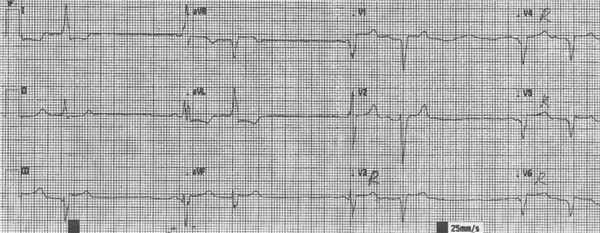

8.6.2.3.Инфаркт миокарда задне-диафрагмальной и задне-базальной локализации (распространенный задний ИМ) обусловлен окклюзией правой коронарной артерии (ПКА) или огибающей артерии (ЛКА), рисунок 139.

Отведения в которых определяются характерные ЭКГ признаки: III, aVF, II, V7-V9.

Реципрокные изменения определяются в отведениях: I, aVL, V1-V4.

Рис. 139. ЭКГ при распространенном заднем инфаркте миокарда.

Элевация сегмента ST II, III, aVF, V7-V9, реципрокная депрессия сегмента ST V1-V3.